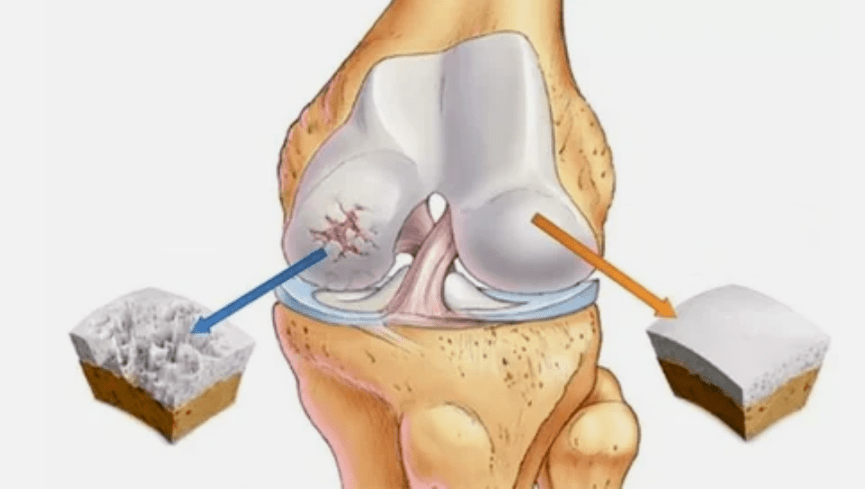

- The primary lesion affects hyalin cartilage.In case of circulatory disorders, a deterioration of the pathological power occurs.This is the first step or the cause, which can occur by osteoarthritis.

- Hyalin coating pathologies.The slimming of the cartilage leads to the replacement of its pathological tissues - bone structures.

- Abnormal growths appear on cartilage - osteophytes.

- The violation in particular of the natural anatomy of cartilage and bones causes the overload of healthy areas of cartilage.The destruction of joint tissues without treatment is increasing constantly and leads to a handicap.

When the degree of disease increases, pathological processes are still aggravated.In the end, all the hyalin cartilage is destroyed.